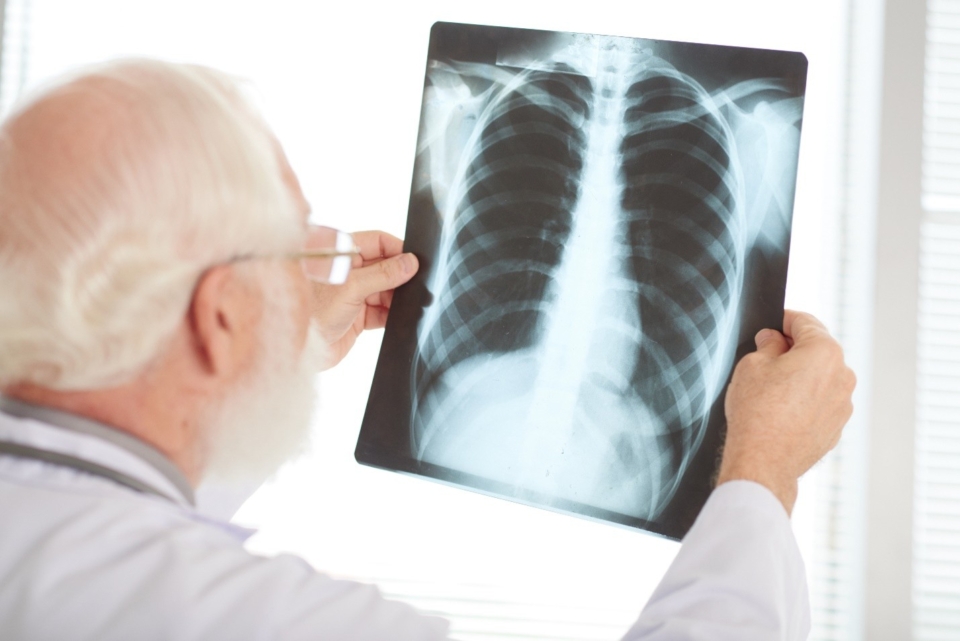

Найчастіше хвороба вражає легені, але патологічний процес може розвиватися і в інших органах та тканинах.